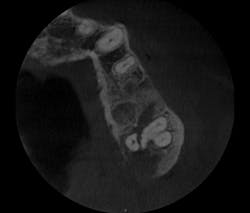

I prescribed a CBCT scan to evaluate site No. 14 prior to implant placement and to evaluate tooth No. 15. After capturing a CBCT scan on the CS 9300 (with a 5 cm x 5 cm field of view and a resolution of 90 ÎĽm), the image clearly showed a palatal root fracture on tooth No. 15 across from the cross-sectional and axial scan views (figs. 1, 2). Thanks to the enhanced diagnostic quality of the images, we decided to extract the tooth.

Figure 1: